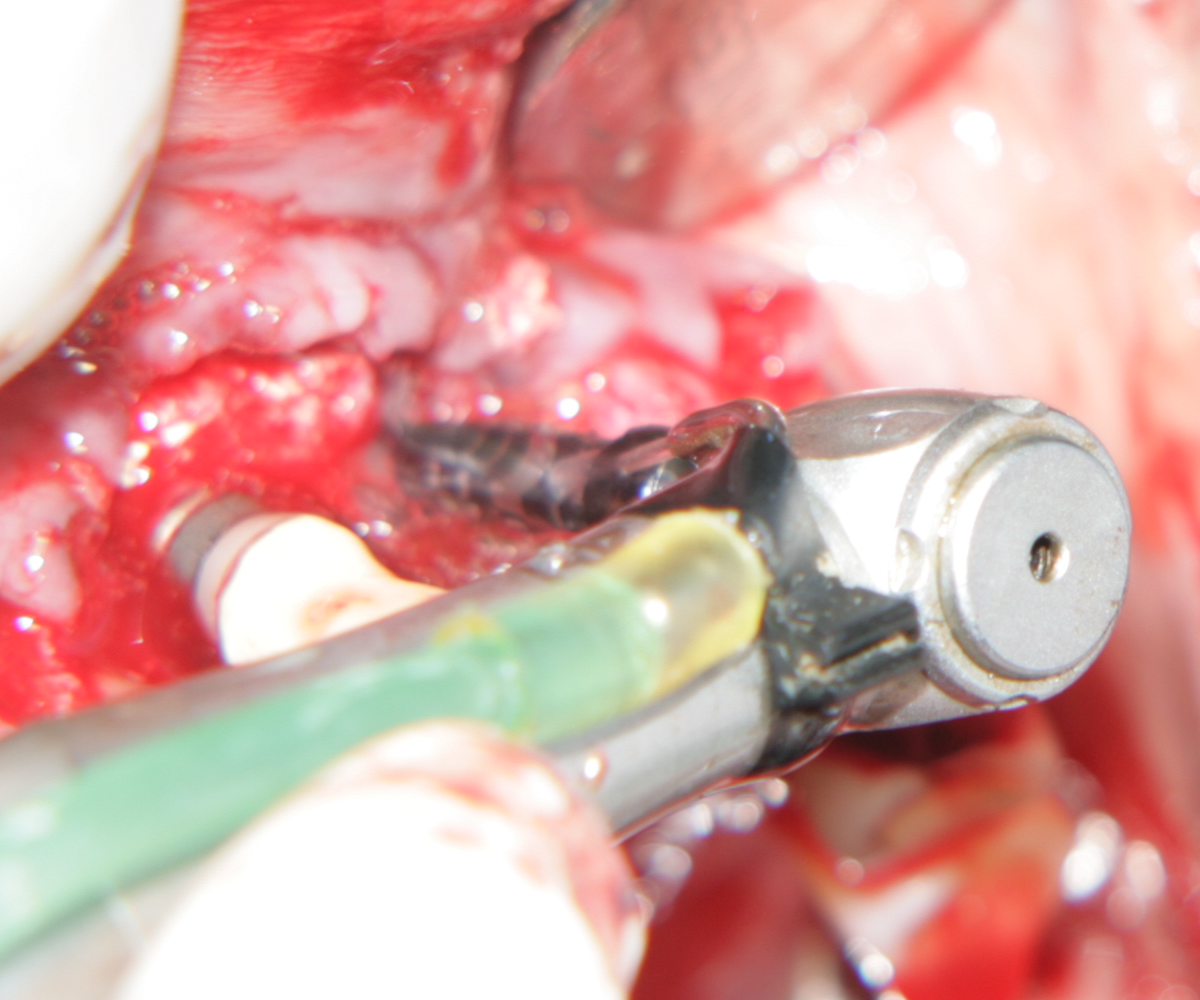

Пробиване с калиброващата фреза. Вижда се

водното охлаждане, което е важно за предпазване на костта от некроза вследствие

загряването

Първоначално разпробиване за имедиатно поставяне на зъбен имплант след

екстракция на долен молар. При горните моларни зъби ситуацията е идентична, но

има три корена вместо два. Идеята е да се центрова пилотната фреза в центъра на

интеррадикуларната септа, при което да се получи оптимално позициониране на

импланта. В много случаи фрезата се приплъзва встрани и започва да пробива във

възможно най-неудачното направление, така че е добре тя да се държи стабилно от

оператора, особено в началото. Добрите пилотни фрези имат силно заострен връх,

който е възможно да бъде поставен в една точка и да не се приплъзва встрани -

дори и при остра септа. При наличие на пародонтален проблем горната част на

преградата е резорбирана и фиксацията на фрезата е технически много по-лесна.

При употребата на

хирургичен водач определянето на правилната посока на разпробиване също е

доста по-лесно.

Много често вместо пилотната фреза от имплантологичния кит е възможно да се

използва класическа фреза за трепанация. Разбира се, тя трябва да бъде с

по-малък диаметър от ширината на избрания зъбен имплант - в противен случай

имплантът няма да може да се завинти в костта и няма да има добра първична

стабилност. Трепанационните фрези нямат свойството да приплъзват встрани -

необходимо е само в рамките на секунда или две да бъдат задържани стабилно, при

което посоката и мястото на разпробиване вече са фиксирани. Допълнително

предимство е възможността да се вземе автогенен костен трансплантат - във

вътрешната част на фрезата остава костен фрегмент, който може да се постави

навсякъде по преценка на оператора. И при двата случая е важно да има обилна

иригация с

физиологичен серум, за да не се загряват костните тъкани.